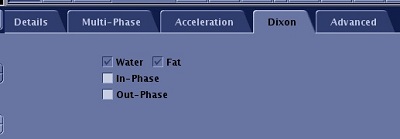

- Click the Dixon tab.

Figure 3. Dixon tab

- The In-Phase and Out-Phase options on the Dixon tab are only available if Flex is selected with DISCO, the default state. Flex generates water-fat separated images and optional source images (in-phase and/or out-of-phase).

- If fat suppression is not needed, do NOT select Flex, SSRF, nor Chem SAT: SPECIAL.